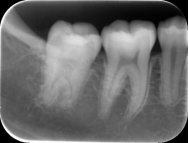

根管治疗前中后

正常患者牙齿片